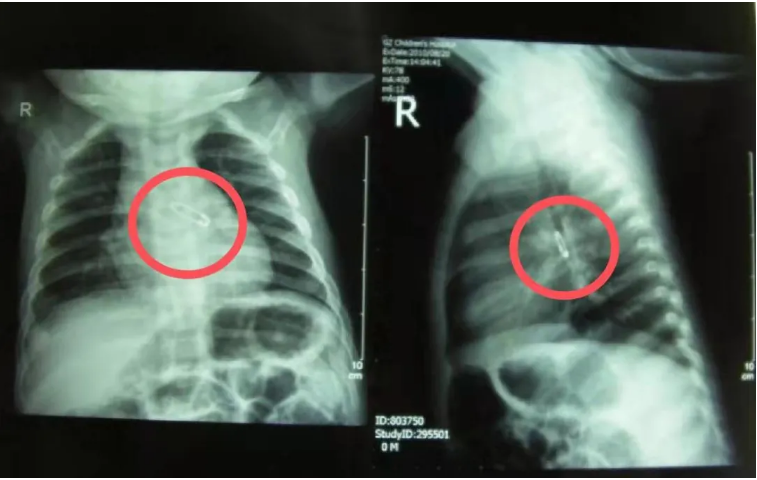

如何预防儿童呼吸道异物?